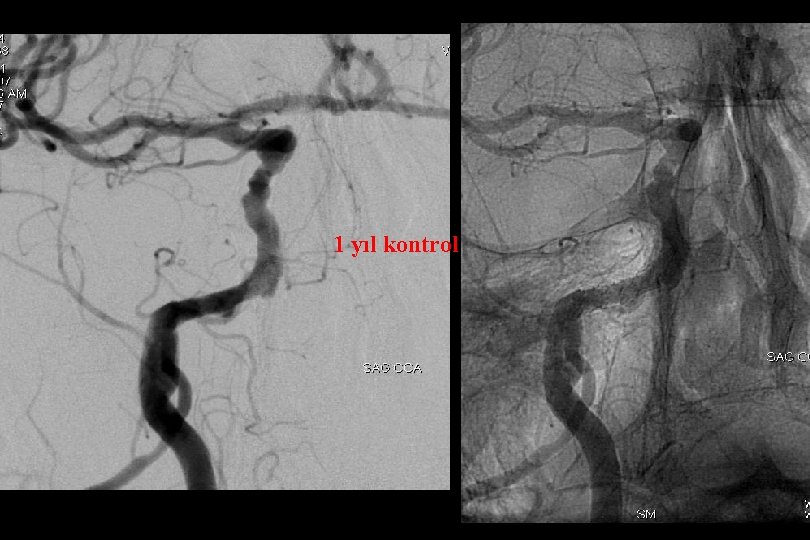

1 yıl kontrol

PTA ve Solitaire ile stentleme sonrası